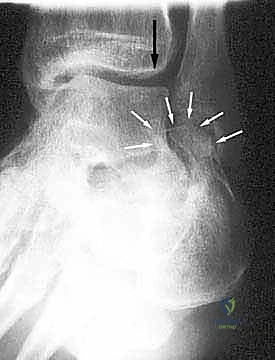

- الأشعة السينية (X-rays) متعددة الزوايا: لتقييم الانهيار العظمي وزوايا الكعب (مثل زاوية بوهلر وزاوية جيسان).

- الأشعة المقطعية ثلاثية الأبعاد (3D CT Scan): وهي الخطوة الذهبية والأهم في عيادة الدكتور هطيف. تتيح هذه الأشعة بناء نموذج ثلاثي الأبعاد دقيق للكعب المشوه، مما يسمح بتحديد أماكن الانحشار العظمي بدقة المليمتر، ومعرفة مدى تلف الأسطح المفصلية. بناءً على هذه الصور، يتم وضع خطة "القطع العظمي التصحيحي" قبل دخول غرفة العمليات.

| ارتفاع الكعب (زاوية بوهلر) | طبيعي (20 إلى 40 درجة)، يدعم قوس القدم | منهار (زاوية مسطحة أو سلبية)، تسطح شديد للقدم |